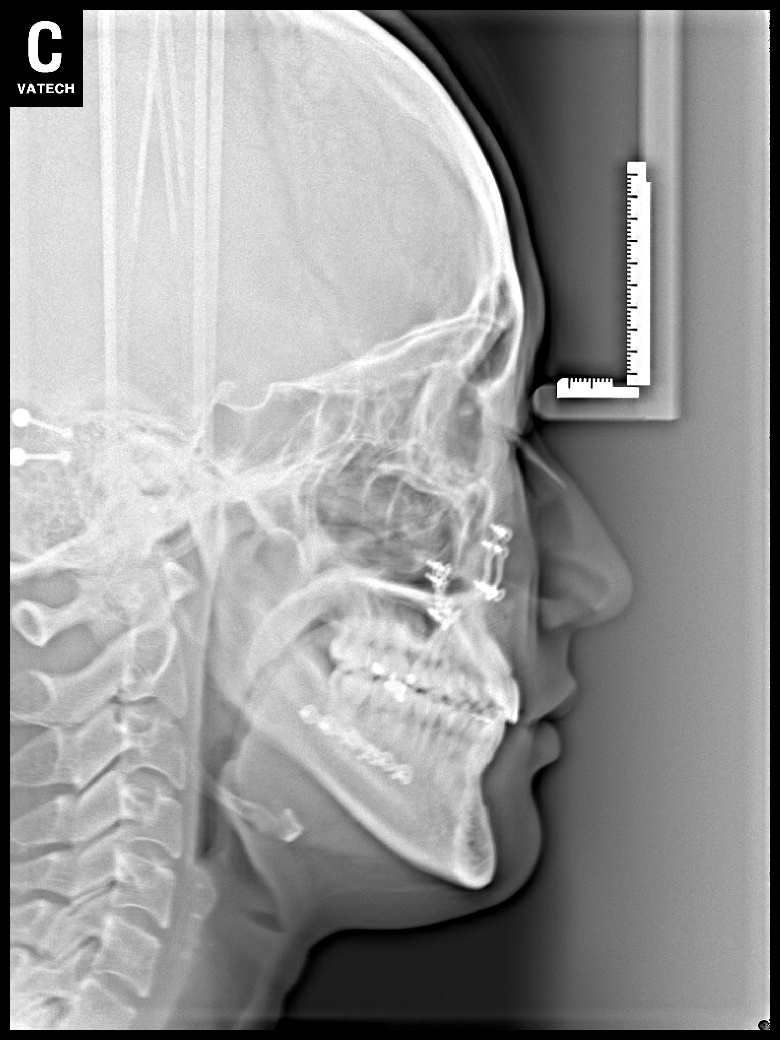

치료 후 사진입니다.